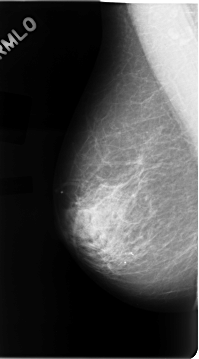

C_0050_1.LEFT_MLO

FILE: C_0050_1.LEFT_MLO.OVERLAY

TOTAL_ABNORMALITIES 1

ABNORMALITY 1

LESION_TYPE MASS SHAPE IRREGULAR MARGINS SPICULATED

ASSESSMENT 5

SUBTLETY 5

PATHOLOGY MALIGNANT

TOTAL_OUTLINES 1

BOUNDARY